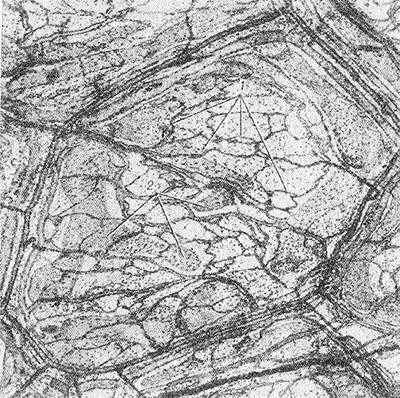

Рис. 2. Схематическое изображение строения стенки кровеносного капилляра: 1 — эндотелиальная оболочка; 2 — базальная оболочка, состоящая из базальной мембраны (3) и перицитов (4), в просвете капилляра видны эритроциты (5).

Рис. 3. Электронограмма фрагмента стенки кровеносного капилляра из околоушной слюнной железы: I — часть эритроцита в просвете капилляра; II — эндотелиоцит (1 — цитоплазма, 2 — микропиноцитозные везикулы); III — базальная мембрана; IV — перицит, расположенный в толще базальной мембраны (3 — цитоплазма, 4 — ядро, 5 — контакт отростка перицита с эндотелиоцитом).

Рис. 4. Электронограмма элементов стенки кровеносных капилляров: а — внутримозговой капилляр (1 — гликопротеидовое покрытие, 2 — эндотелиоцит); х 60 000; б — межклеточный контакт в эндотелиальной оболочке гломерулярного капилляра почки (1 — цитоплазма соседних эндотелиоцитов, 2 — контактирующие цитолеммы, 3 - межмембранный промежуток); х 90 000; в и г — гломерулярные капилляры почки (1 - открытые фенестры; 2 — диафрагмальные фенестры в цитоплазме эндотелиоцитов); X 70 000; д — стенка синусоидного капилляра печени (1 — прерывистый контакт между смежными эндотелиоцитами 2); х 35 000.

Как показали электронно-микроскопические наблюдения, стенка кровеносного К., часто называемая капиллярной мембраной, состоит из двух оболочек: внутренней — эндотелиальной и наружной — базальной. Схематическое изображение строения стенки кровеносного К. представлено на рисунке 2, более детальное — на рисунках 3 и 4.

Эндотелиальная оболочка образована уплощенными клетками — эндотелиоцитами (см. Эндотелий). Число эндотелиоцитов, ограничивающих просвет К., обычно не превышает 2—4. Ширина эндотелиоцита колеблется от 8 до 19 мкм и длина — от 10 до 22 мкм. В каждом эндотелиоците выделяют три зоны: периферическую, зону органелл, ядросодержащую зону. Толщина этих зон и их роль в обменных процессах различны. Половину объема эндотелиоцита занимают ядро и органеллы — пластинчатый комплекс (комплекс Гольджи), митохондрии, зернистая и незернистая сеть, свободные рибосомы и полисомы. Органеллы сконцентрированы вокруг ядра, вместе с к-рым составляют трофический центр клетки. Периферическая зона эндотелиоцитов выполняет в основном обменные функции. В цитоплазме этой зоны располагаются многочисленные микропиноцитозные везикулы и фенестры (рис. 3 и 4). Последние представляют собой субмикроскопические (50—65 нм) отверстия, которые пронизывают цитоплазму эндотелиоцитов и бывают перекрыты истонченной диафрагмой (рис. 4, в, г), являющейся дериватом клеточной мембраны. Микропиноцитозные везикулы и фенестры, участвующие в трансэндотелиальном переносе макромолекул из крови в ткани и обратно, в физиологии называют крупными «норами». Каждый эндотелиоцит покрыт снаружи тончайшим слоем продуцируемых им гликопротеидов (рис. 4, а), последние играют немаловажную роль в поддержании постоянства микросреды, окружающей клетки эндотелия, и в адсорбции веществ, транспортируемых через них. В эндотелиальной оболочке соседние клетки объединяются с помощью межклеточных контактов (рис. 4, б), состоящих из цитолемм смежных эндотелиоцитов и межмембранных промежутков, заполненных гликопротеидами. Эти промежутки в физиологии чаще всего отождествляют с мелкими «порами», через которые проникают вода, ионы и белки с низким молекулярным весом. Пропускная способность межэндотелиальных промежутков различна, что объясняется особенностями их строения. Так, в зависимости от толщины интерцеллюлярной щели различают межэндотелиальные контакты плотного, щелевого и прерывистого типов. В плотных контактах интерцеллюлярная щель на значительном протяжении полностью облитерирована благодаря слиянию цитолемм смежных эндотелиоцитов. В щелевых контактах величина наименьшего расстояния между мембранами соседних клеток колеблется между 4 и 6 нм. В прерывистых контактах толщина межмембранных промежутков достигает 200 нм и более. Межклеточные контакты последнего типа в физиологической литературе также отождествляют с крупными «порами».

Базальная оболочка стенки кровеносного К. состоит из клеточных и неклеточных элементов. Неклеточный элемент представлен базальной мембраной (см.), окружающей эндотелиальную оболочку. Большинство исследователей рассматривает базальную мембрану как своеобразный фильтр толщиной 30—50 нм с размерами пор, равными — 5 нм, в к-ром сопротивление проникновению частиц возрастает с увеличением диаметра последних. В толще базальной мембраны расположены клетки — перициты; их называют адвентициальными клетками, клетками Руже, или интрамуральными перицитами. Перициты имеют вытянутую форму и изогнуты в соответствии с внешним контуром эндотелиальной оболочки; они состоят из тела и многочисленных отростков, которые оплетают эндотелиальную оболочку К. и, проникая через базальную мембрану, вступают в контакты с эндотелиоцитами. Роль этих контактов, так же как и функции перицитов, достоверно не выяснена. Высказано предположение об участии перицитов в регуляции роста эндотелиальных клеток К.

Кровеносные Капилляры разных органов и тканей обладают типовыми особенностями строения, что связано со спецификой функции органов и тканей. Принято различать три типа К.: соматический, висцеральный и синусоидный. Стенка кровеносных капилляров соматического типа характеризуется непрерывностью эндотелиальном и базальной оболочек. Как правило, она малопроницаема для крупных молекул белка, но легко пропускает воду с растворенными в ней кристаллоидами. К. такой структуры обнаружены в коже, скелетной и гладкой мускулатуре, в сердце и коре полушарий большого мозга, что соответствует характеру обменных процессов в этих органах и тканях. В стенке К. висцерального типа имеются окошки — фенестры. К. висцерального типа характерны для тех органов, которые секретируют и всасывают большие количества воды и растворенных в ней веществ (пищеварительные железы, кишечник, почки) или же участвуют в быстром транспорте макромолекул (эндокринные железы). К. синусоидного типа обладают большим просветом (до 40 мкм), что сочетается с прерывистостью их эндотелиальной оболочки (рис. 4, д) и частичным отсутствием базальной мембраны. К. этого типа обнаружены в костном мозге, печени и селезенке. Показано, что через их стенки легко проникают не только макромолекулы (напр., в печени, к-рая продуцирует основную массу белков плазмы крови), но и клетки крови. Последнее характерно для органов, участвующих в процессе кроветворения.